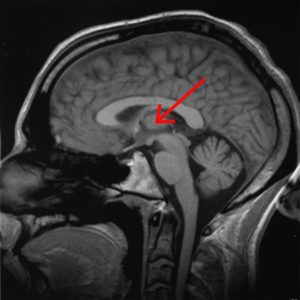

দীর্ঘদিন ব্যাপী স্বাত্ত্বিক জীবনে ও নিয়মিত ধ্যানে অভ্যস্ত কোন ব্যক্তি চাইলে গভীরতর ধ্যানে মগ্ন হতে সক্ষম হন যে ধ্যানমগ্ন অবস্থায় গামা তরঙ্গ শুধু পূর্বোক্ত নিউরাল লুপগুলিতে সীমাবদ্ধ না থেকে মস্তিষ্কের বহু অংশে যেমন “থ্যালামাস”, “ভিসুয়াল কর্টেক্স”-এ কর্টিকাল থিটা তরঙ্গ ও আলফা তরঙ্গ-র প্রভাবকে খর্ব করে রাজত্ব শুরু করে। এইভাবে দীর্ঘক্ষণ ধ্যানমগ্ন থাকলে উচ্চ কম্পাঙ্কের গামা তরঙ্গের প্রভাবে যদি থ্যালামাস খুব অল্পও ক্ষতিগ্রস্ত হয়, মস্তিষ্কে গামা তরঙ্গের প্রবাহ সঙ্গে সঙ্গে চিরকালের জন্য বন্ধ হয়ে যায়। আগেই বলেছি যে গামা তরঙ্গের প্রবাহ মস্তিষ্কে “স্পেস” ও “টাইম”-র ধারণা সৃষ্টি করে। বস্তুত গামা তরঙ্গই সেরিব্রাল কর্টেক্স ও থ্যালামাস সংযোগকারী নিউরাল লুপগুলির সাথে সেরিব্রাল কর্টেক্স ও মিডব্রেইন সংযোগকারী নিউরাল লুপগুলির রেজোনেন্স ঘটিয়ে মস্তিষ্কে তৈরি করে “স্পেস-টাইম কন্টিনিউয়াম”-র ধারণা। তাই মস্তিষ্কে গামা তরঙ্গের প্রবাহ চিরতরে বন্ধ হলে মস্তিষ্কের “স্পেস-টাইম কন্টিনিউয়াম”-র ধারণাও চিরতরে বিলুপ্ত হয়, অন্যভাবে বলা যায় যে ধ্যানমগ্ন ব্যক্তিটির মস্তিষ্ক চিরতরে “কোমা”-য় চলে যায় !